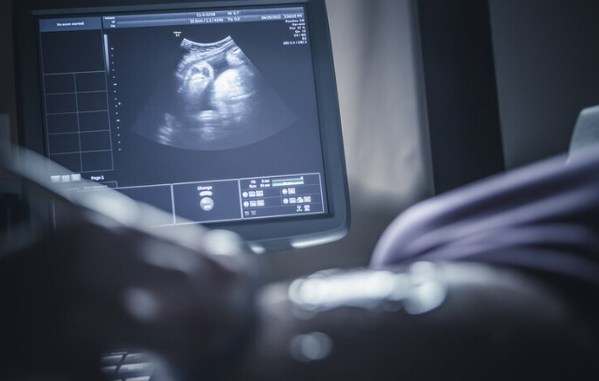

پزشک شما در طول معاینات پیش از زایمان (معمولاً در سه ماهه اول) بارداری پوچ را تشخیص میدهد. سونوگرافی رحم اغلب به جای جفت، چندین کیسه پر از مایع را نشان میدهد و معمولاً در این حالت هیچ جنینی وجود ندارد. علاوه بر این در بارداری پوچ، hCG در سطوح غیرطبیعی بالا تولید میشود. انجام آزمایش هورمونی و خون در آزمایشگاه میتواند این سطوح بالا را که یک زنگ خطر مهم است تشخیص دهد.